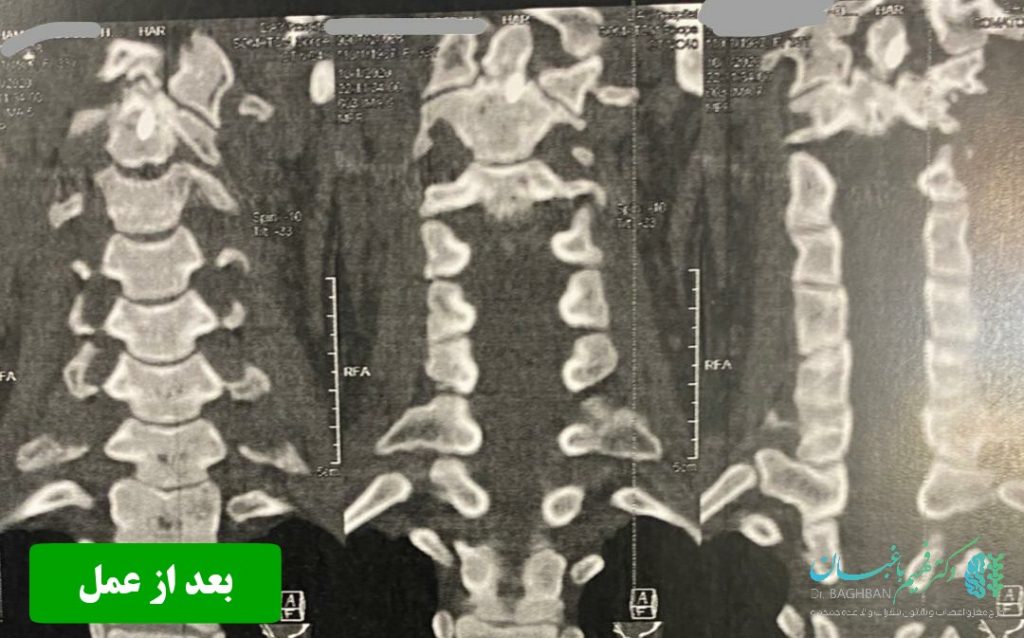

بیمار خانم جوان با سابقه ضربه شدید گردن و شکستگی زائده ادونتویید مهره دوم گردن که تحت عمل جراحی قرار گرفتند. تصاویر قبل و بعد از عمل را در زیر مشاهده می نمایید . همچنین توضیحات دکتر باغبان را در حین جراحی در ویدئوی انتهای مقالات مشاهده کنید. (ویدئو حاوی تصاویر جراحی می باشد)

تصاویر بعد از عمل